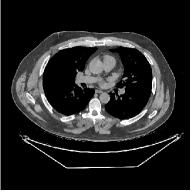

This section compares the reconstruction quality and runtime among the proposed MBIR method, PWLS-ST-, and other three MBIR methods, PWLS-EP, PWLS-DL, and PWLS-ST-. Table I shows that, for both 2D and 3D sparse-view CT reconstructions of the XCAT phantom, the proposed PWLS-ST- model outperforms PWLS-EP and PWLS-ST- in terms of RMSE. In addition, PWLS-ST- using a square transform (of size ) achieves lower RMSE than PWLS-DL using an overcomplete dictionary (of size ) for 2D sparse-view reconstructions. Fig. 3(a) and Fig. 4 show the reconstructed images for 2D and 3D phantom experiments, with different reconstruction models and different number of views. (See the corresponding error maps in the supplement.) The proposed PWLS-ST- consistently gives more accurate image reconstructions compared to other MBIR methods. Specifically, PWLS-ST- has smaller errors in the heart region (see zoom-ins in Fig. 3(a)) of 2D reconstructions than PWLS-DL and PWLS-ST-. In addition, compared to PWLS-ST-, PWLS-DL and PWLS-ST- have some ringing artifacts around the edges with high transition, e.g., edges between air and soft tissues. (See a comparison of profiles of PWLS-ST- and PWLS-ST- in the supplement.) In particular, PWLS-ST- and PWLS-DL give more visible ringing artifacts for 2D reconstruction from fewer views, and PWLS-ST- has these ringing artifacts for 3D reconstructions regardless of the number of views (see zoom-ins in Fig. 4). Table II reports runtimes of different MBIR methods in reconstructing the -views XCAT phantom scan. (FBPConvNet is a non-MBIR method and its runtime for processing a image is approximately one second with a TITAN Xp GPU.) While providing better reconstruction quality, the proposed Algorithm 1 of PWLS-ST- has shorter runtime compared to the algorithms of PWLS-DL and PWLS-ST- in Section III-A. Similar to the PWLS-EP algorithm, the reconstruction time of the PWLS-DL, PWLS-ST-, and PWLS-ST- algorithms can be further reduced by using ordered subsets [51].

Fig. 3(b) shows that when tested on the clinical scan data, the proposed PWLS-ST- method improves reconstruction quality in terms of noise and artifacts removal (e.g., see zoom-ins for soft-issue regions), and edge preservation (e.g., see zoom-ins for bone regions), compared to PWLS-EP and PWLS-ST-. Compared to PWLS-DL, PWLS-ST- achieves comparable image quality, but requires less computational complexity.

![]() |

| (a) 2D fan-beam CT experiments |

| (b) 3D axial cone-beam CT experiments |